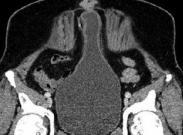

臍尿管未閉導致臍尿管瘺臨床較罕見,以臍孔漏尿為主要特征,并發感染時可出現局部癥狀。膀胱內注入亞甲藍觀察漏出液有否藍染,瘺孔內注入造影劑、排泄性膀胱尿道造影或膀胱造影可確診。治療方法為手術切除瘺管,由于部分患者可能存在下尿路梗阻,應注意解除梗阻。